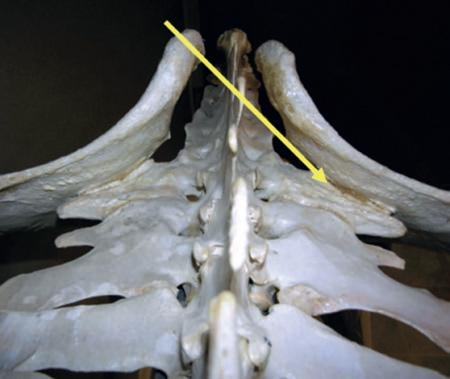

Annie Lambert talks to Dr. Michael Manno about dilemmas the Sacroiliac joint can pose and how to deal with these.

• The neck: It is shocking how many abnormalities are visible with 3-dimensional imaging of the neck. Nerve compression is visible even when it comes from the side; previously undiagnosable with regular radiographs.